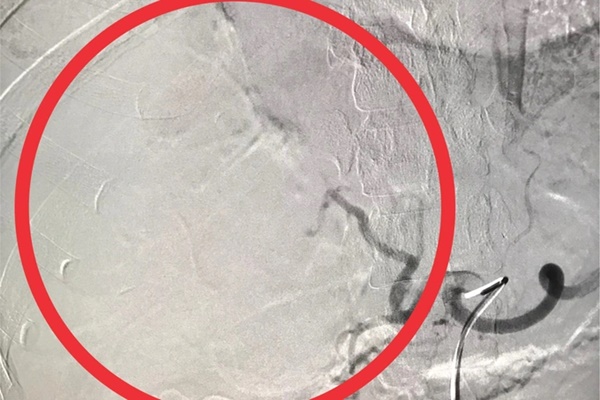

Sau đó, chị L. được chỉ định thực hiện thủ thuật can thiệp chụp và nút mạch cầm máu gan trên hệ thống máy chụp mạch số hóa xóa nền (DSA), kết hợp vật liệu tắc mạch vào động mạch gan phải để tiến hành cầm máu gan vỡ.

"Thủ thuật diễn ra trong vòng 40 phút. Sau can thiệp, hiện tại tình trạng bệnh nhân tỉnh, mạch huyết áp ổn định, tiếp xúc tốt, giảm đau bụng. Dự kiến sẽ được xuất viện trong vài ngày tới", bác sĩ của bệnh viện thông tin.

Và sau khi được điều trị (Ảnh: BV cung cấp).